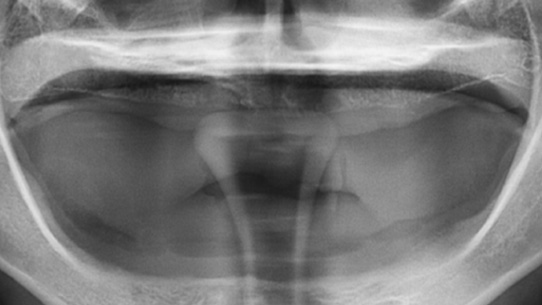

틀니가 번번히 탈락되어 일상생활이 불편하셔서 내원, 고정력이 없는 틀니를 사용하여 잇몸 염증과 통증 있으셨습니다. 상악의 경우

틀니를 오랫동안 착용하여 잇몸 뼈 소실이 심해 일반 틀니를 제작하고, 하악의 경우 임플란트 2개를 식립 후 임플란트 틀니를 제작해 드렸습니다.

상악은 잇몸뼈의 손실이 심한 상태

하악에 임플란트 2개 식립